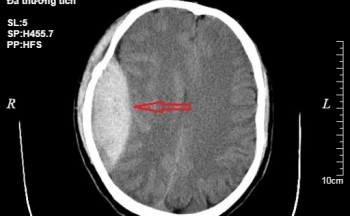

Phẫu thuật cứu sống bệnh nhân ngã từ độ cao 3m

Thông tin từ BV Đa khoa Hùng Vương, đơn vị này vừa phẫu thuật cứu sống bệnh nhân ngã từ độ cao 3m.